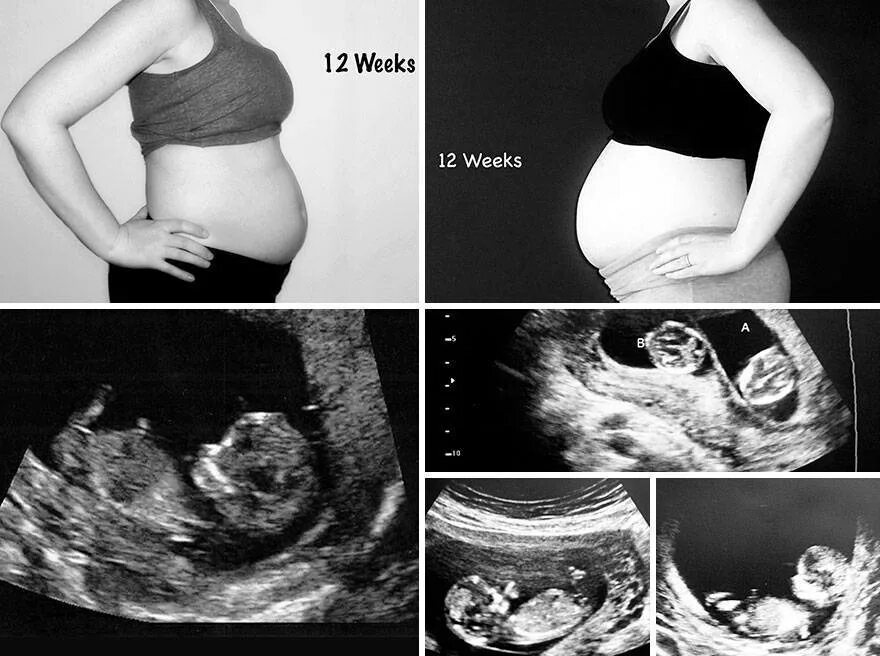

7 12 недель